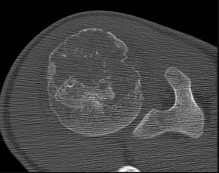

Based on the Schatzker classification, a bicondylar tibial plateau fracture with complete dissociation of the metaphysis from the diaphysis is classified as:

Explanation

A Schatzker VI fracture is defined by complete metaphyseal-diaphyseal dissociation, often accompanied by severe soft tissue injury. Schatzker V is a bicondylar fracture but maintains continuity between the articular segment and the diaphysis. Schatzker I-III involve the lateral plateau, and IV involves the medial plateau.